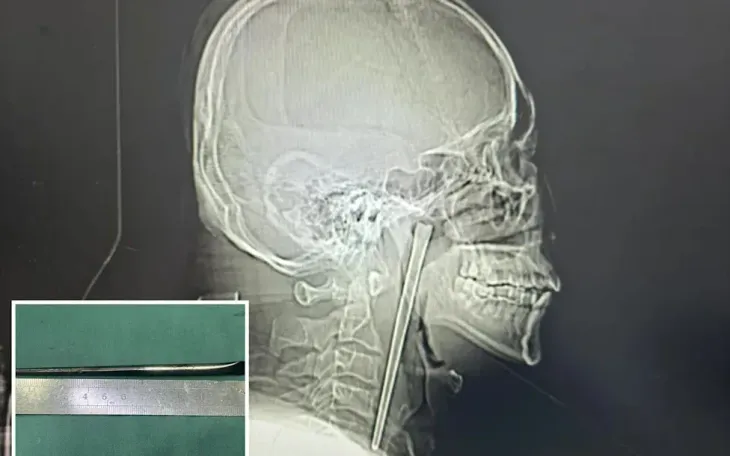

Ảnh chụp X-quang chiếc đũa dài khoảng 12 cm nằm trong cổ họng bệnh nhân. Ảnh: YouTube

Nhóm phẫu thuật đã lựa chọn phương pháp can thiệp ít xâm lấn, đưa dụng cụ qua đường miệng để lấy dị vật thay vì tiến hành mổ mở vùng cổ. Ca phẫu thuật diễn ra thành công, chiếc đũa kim loại được lấy ra an toàn.